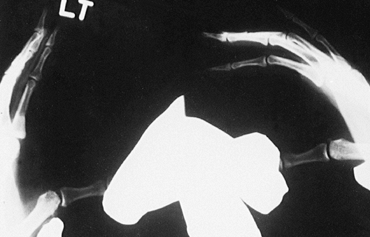

Figure 39.9. A:

AP radiograph with lateral stress applied to the proximal interphalangeal joint. Lateral deviation of more than 20° is indicative of a complete collateral ligament injury. B: Fluoroscopic stress view of the thumb MP joint showing lateral subluxation of the proximal phalanx. |